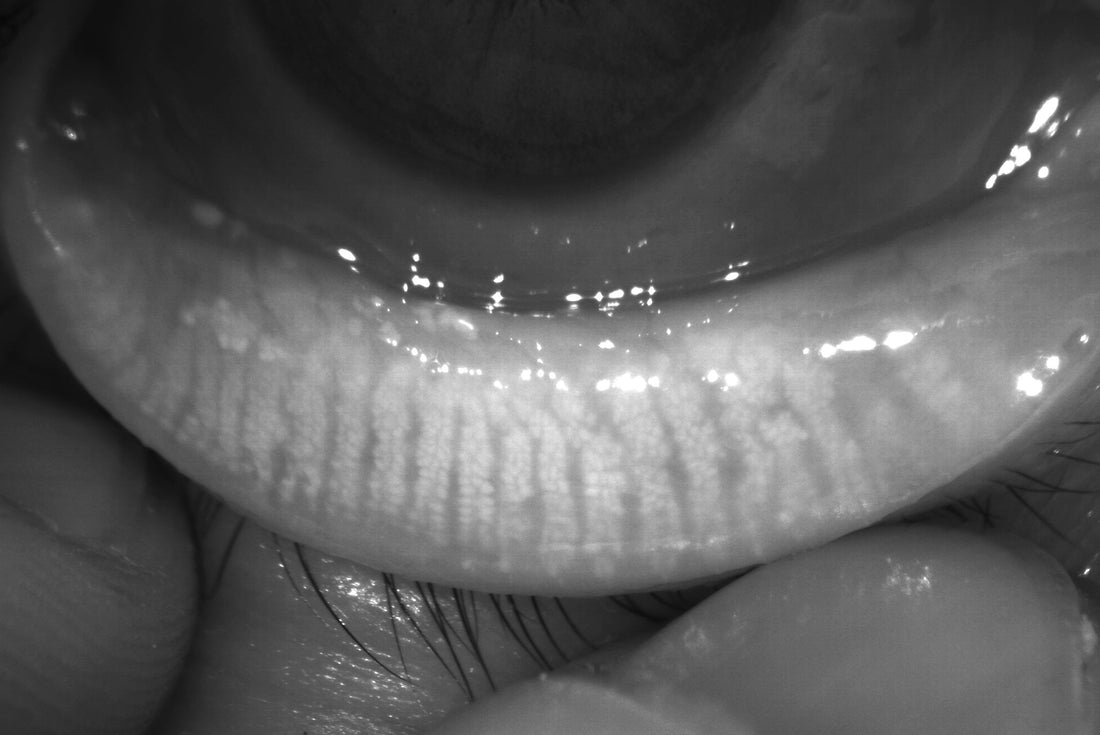

Insurance reimbursement hinges on demonstrating medical necessity. Anterior segment photography, which documents conditions of the external eye, lids, or adnexa (e.g., cornea, conjunctiva, anterior chamber), is reimbursable when:

• It aids in diagnosis or treatment planning (e.g., documenting blepharitis severity or post-surgical changes).

• Corneal disorders (e.g., keratitis, dystrophies).

• MGD

• Eyelid conditions (e.g., chalazion, neoplasms).